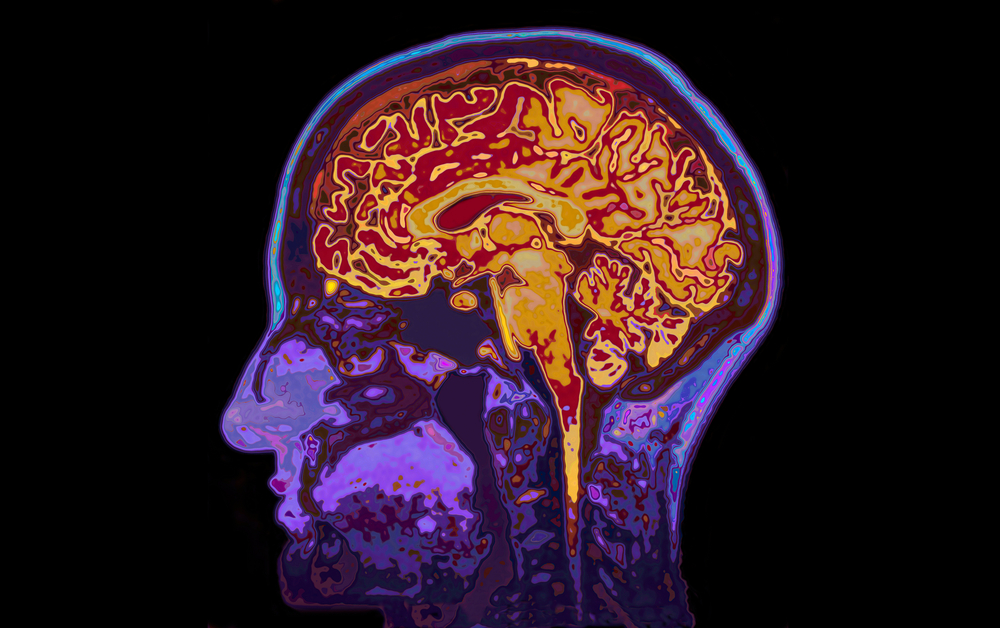

Roma, 20 maggio 2022 (AgOnb) – Oligodendrociti: è questo il nome di alcune cellule del cervello, dotate di una specie di “kit anti-invecchiamento”, specializzate nel fornire sostegno e protezione ai neuroni. Un’eredità nascosta, che si innesca esclusivamente in presenza di un pericolo, la cui scoperta potrebbe ora portare a sviluppare nuove strategie per tutelare il cervello nelle persone più anziane e terapie contro le malattie neurodegenerative. A realizzare la scoperta un team di ricercatori italiani, grazie ad uno studio sui topi i cui risultati sono stati pubblicati sulla rivista “Nature Communications”. Il gruppo di esperti, coordinato dagli esperti dell’Università di Torino in collaborazione con colleghi statunitensi, ha rimarcato come gli oligodendrociti siano famosi per essere le cellule cerebrali responsabili della produzione, nello specifico, della guaina di mielina che assicura la conduzione dei segnali fra i neuroni. Fino ad oggi, però, nessuno era stato in grado di comprendere se e quanto queste cellule fossero diverse fra loro e quanto la loro eterogeneità potesse impattare sulla fisiologia o sulla patologia del sistema nervoso centrale. (AgOnb) Des 12:00